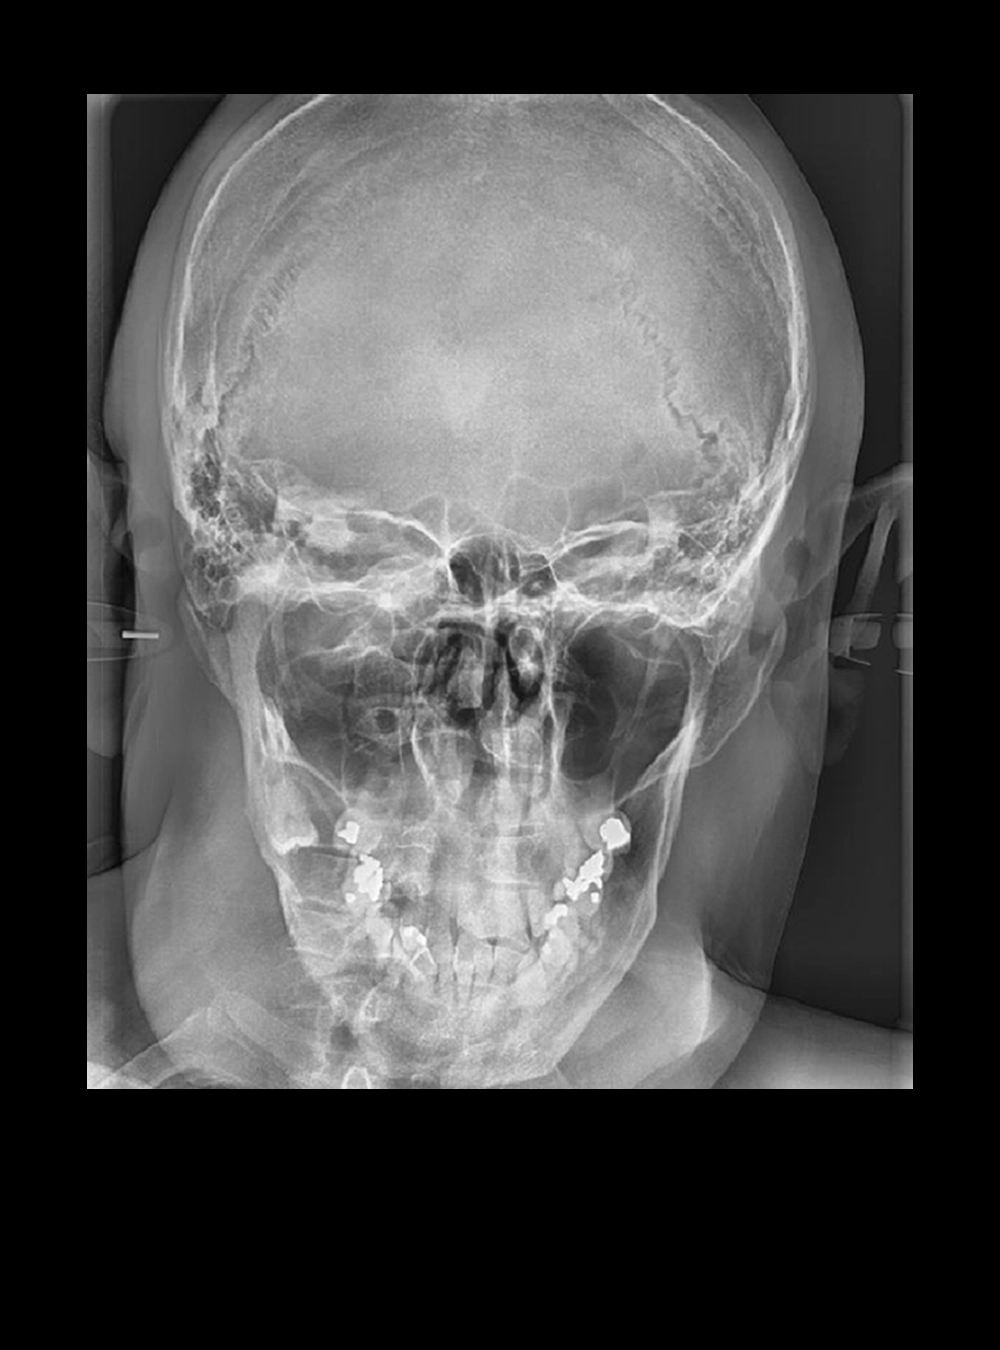

Rx Frontal Caldwell

Rx Frontal Proyección Waters

• Waters de Cráneo

• Cadwell